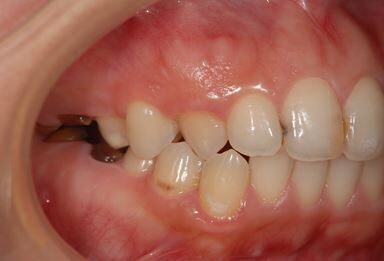

セラミック治療+骨造成(欠損部)

| 性別/年齢 | 女性 / 34歳 | ||||||||||||||||||||||||||||||||

| 主訴 | 前歯と奥歯の虫歯と、前歯の歯並び(でこぼこ)・歯の形(小さくとがった形が気になる)を治したい。 | ||||||||||||||||||||||||||||||||

| 治療方針 | 上顎前歯1歯抜歯し、オールセラミックブリッジ、クラウン、ラミネートベニアにて審美的回復を行う。 | ||||||||||||||||||||||||||||||||

| 治療内容 | オールセラミッククラウン2本、ジルコニアフレームオールセラミックブリッジ3本、オールセラミックラミネートベニア2本、骨造成(欠損部) | ||||||||||||||||||||||||||||||||